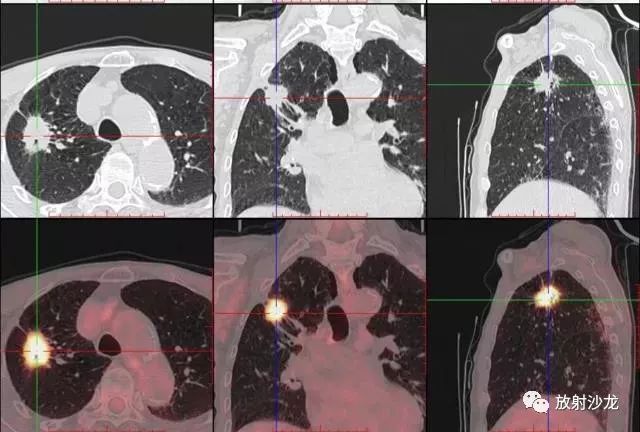

PET-CT等于PET+CT,包含PET(功能分子影像)與CT(解剖影像)的最優(yōu)化組合;即同時具有PET和CT的功能,但它絕不是二者功能的簡單疊加,因為PET與CT優(yōu)勢互補,“1+1>2”。PET-CT除了具備PET和CT各自的功能外,其獨有的融合圖像,將PET圖像與CT圖像融合, 可以同時反映病灶的代謝,可以早期診斷疾病的同時,明顯提高診斷的準確性。

18F-FDG(氟脫氧葡萄糖)是葡萄糖的類似物,是臨床最常用的顯像劑;18F-FDG能反映體內(nèi)葡萄糖利用狀況。腫瘤細胞內(nèi)可積聚大量18F-FDG,但是18F-FDG僅僅是葡萄糖類似物,腫瘤細胞攝取后不能進一步代謝,屬于“只進不拉”,能在腫瘤細胞內(nèi)積聚,經(jīng)PET-CT顯像可顯示腫瘤的部位、形態(tài)、大小、數(shù)量及腫瘤內(nèi)的放射性分布。同時腫瘤細胞的原發(fā)灶和轉(zhuǎn)移灶具有相似的代謝特性,一次注射18F-FDG就能方便地進行全身顯像,18F-FDG PET-CT全身顯像對于了解腫瘤的全身累及范圍具有獨特價值。